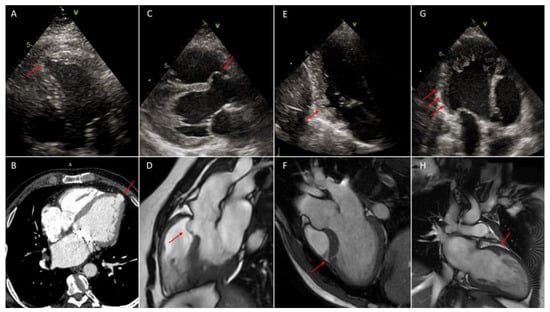

For the diagnosis of left ventricular outpouchings, echocardiography should be the initial diagnostic tool because it is inexpensive, reproducible and demonstrates localization, relation to adjacent structures and eventual associated congenital heart abnormalities [23] (Figure 2 and Figure 3). However, both VD and VA are difficult to see in a certain location [1]; therefore, in growing children or in adult echocardiography may not be sufficient as diagnostic tools for VD or VA, and CMR or CCT can be other second level diagnostic methods [8,9] (Figure 2 and Figure 3). Typical findings in CCT for VD are protruding structures with a sac-like or tube-like shape and narrow orifice from the ventricular lumen. Typically, the differential diagnosis with trabeculation is made with the lesion depth of at least half of the ventricular wall or >5 mm in the right ventricular wall [11]. The utility of evaluation of VA with CCT is more debated since it can provide information on coronary artery anatomy in order to exclude secondary causes of VA. CCT should be used for evaluation of morphology and tissue characteristics only when echocardiography is not conclusive and CMR is unavailable [27].

4.2.4. Diagnosis

As demonstrated in different studies, two-dimensional echocardiography is not able to detect such small structures; to the contrary, CMR and CT are the best cardiac modalities to make a diagnosis of crypts (Figure 2 and Figure 3) [18,19]. CMR allows us to assess the invagination’s disappearance through the myocardial wall during the diastolic phase and thus differentiate between crypts and recesses. Furthermore, both entities are characterized by normal signal intensity because fibrosis is rarely present in patients with sarcomeric mutation and without expressed hypertrophy. In Germans et al.’s study, areas of focal fibrosis were identified only in carrier patients and were limited to hypertrophied myocardial areas [18].

Figure 3. In all figures red arrows indicate the lesion. (A): left ventricular apical diverticulum, 2D-Multimodality imaging of outpouchings/invaginations. Echocardiography in apical four chambers view; (B): left ventricular apical diverticulum, cardiac contrast-enhanced computer tomography (CCT); (C): left ventricular congenital septal aneurysm in left ventricular non-compaction (LVNC), 2D-echocardiography in parasternal long axis (PLAX) view; (D): left ventricular congenital septal aneurysm, cardiac magnetic resonance (CMR); (E): inferior basal myocardial crypt; 2D-echocardiography in apical two chambers view; (F): myocardial crypt of the mid antero-septal wall in hypertrophic phenotype of basal septum, CMR; (G): multiple myocardial recesses in (LVNC), 2D-echocardiography in apical parasternal long axis (APLAX) view; (H): myocardial recess in left ventricular non-compaction (LVNC), CMR.